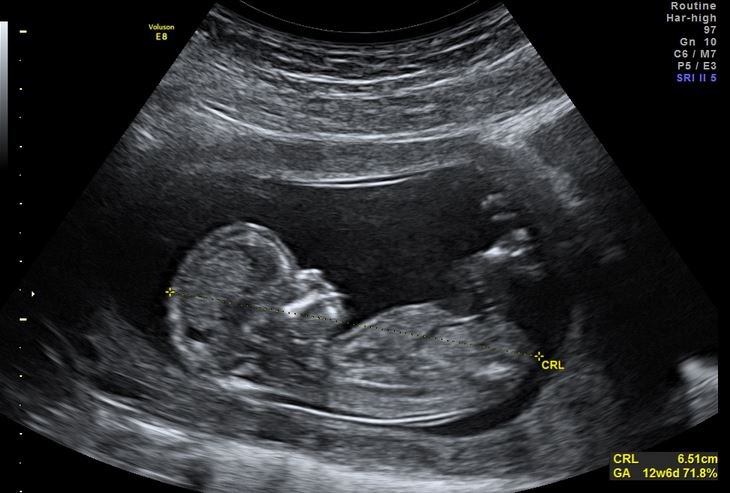

Tel que LifeNews l’avait auparavant rapporté, la technique générale utilisée pour la réduction sélective consiste à plonger une aiguille remplie de chlorure de potassium dans le cœur du bébé visé. Peu de temps après que le produit chimique pénètre le cœur du bébé, le bébé cesse de bouger et son cœur s’arrête. Ce type d’avortement est pratiqué de 9 à 13 semaines de la grossesse pour s’assurer que les corps des bébés morts soient dissous et dans certains cas, le bébé se déplace avant de mourir.